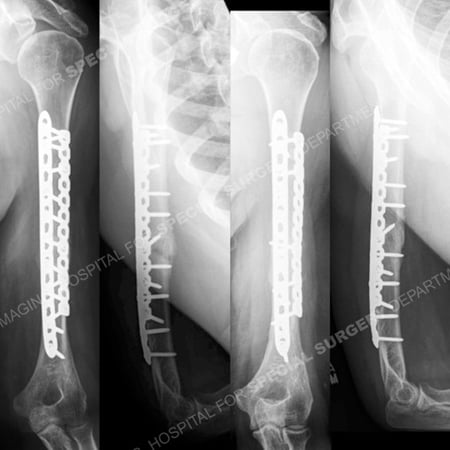

Anteroposterior and lateral radiographs 7 weeks following surgery (left images) revealing early callus formation and adequate hardware positioning and anteroposterior and lateral radiographs at 13 months (right images) illustrating a healed humerus fracture in excellent alignment.